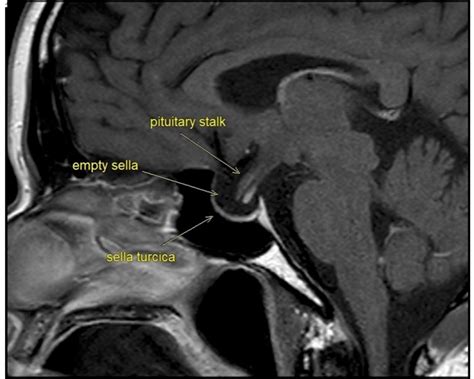

To understand this condition, we must first look at the sella turcica—a bony, saddle-shaped depression at the base of the skull that houses and protects the pituitary gland. In a typical anatomy, the sella is filled primarily by the pituitary gland itself. However, in individuals with an Empty Sella Syndrome (ESS), the sella appears "empty" on imaging results like an MRI or CT scan because it has become filled with cerebrospinal fluid (CSF).

When the condition is classified as a Partial Empty Sella, it means that the sella is only partially filled with CSF, while a significant portion of the pituitary gland remains in its expected position. This can occur due to a defect in the diaphragm sellae—the fold of dura mater that usually acts as a barrier between the brain and the pituitary gland. If this seal is weak, the increased pressure of the CSF can push into the sella, flattening the gland against the bony walls.

If a doctor suspects you have a Partial Empty Sella, they will likely start with an MRI scan, as it provides the most detailed look at the brain structure. Once the imaging confirms the finding, the focus shifts from the "empty" space to the functionality of the gland. A comprehensive evaluation usually involves: